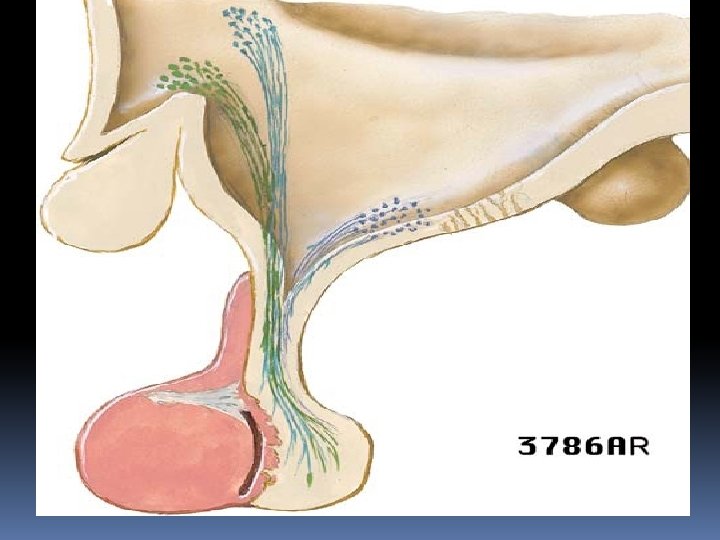

The pituitary gland derives its blood supply from two groups of arteries. The superior hypophyseal artery (SHA) primarily supplies the anterior lobe, whereas the inferior hypophyseal artery (IHA) is primarily related to the pars nervosa. The SHA can arise from the supraclinoid portion of the internal carotid artery (ICA) or from the posterior communicating artery, whereas the IHA arises from the meningohypophyseal trunk, a branch of the cavernous segment of the ICA